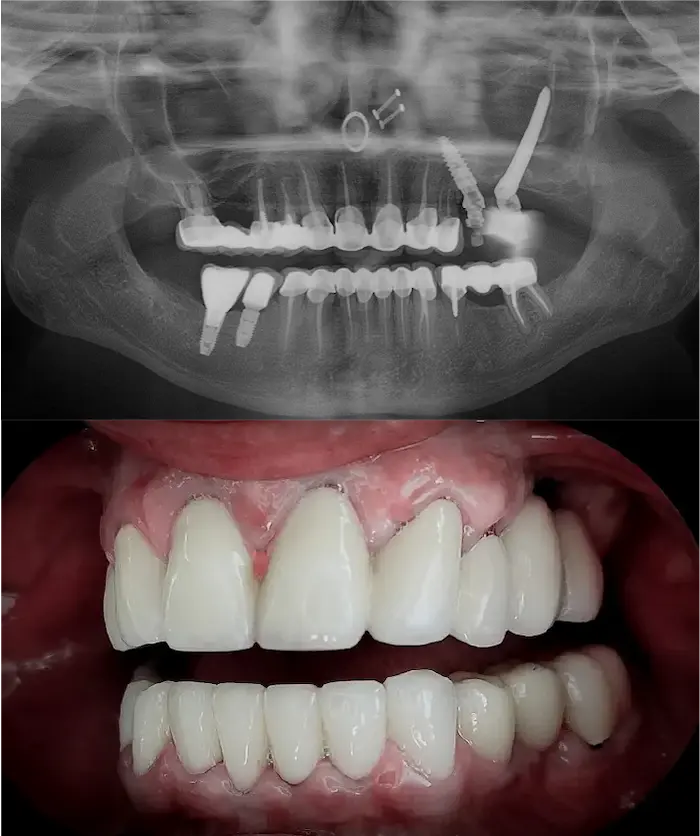

Soluzione di implantologia avanzata indicata in casi di atrofia dell’arcata superiore, quando gli impianti tradizionali o l’All-On non sono utilizzabili.

Zygoma Quad

Zygoma Hybrid

Zygoma Laterale

Gli impianti dentali zigomatici fissi sono impianti in titanio lunghi 3 – 6 cm che si ancorano all’osso zigomatico, molto più denso e stabile dell’osso mascellare. In base alle necessità il chirurgo definirà se utilizzare un impianto Zygoma Quad (due impianti zigomatici per lato), Zygoma Hybrid oppure Zygoma Laterale.

La soluzione di implantologia d’avanguardia quando non è possibile inserire impianti All-on o impianti zigomatici.

Gli impianti sottoperiostei (o impianti subperiostali) vengono creati su misura, in titanio puro T4 completamente biocompatibile, e applicati sulla superficie dell’osso residuo.

Sono progettati digitalmente per adattarsi alla tua anatomia in presenza di atrofia ossea severa.